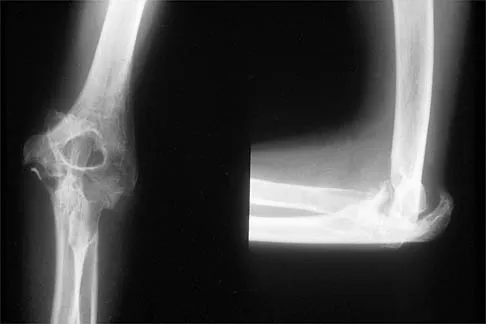

Question 16

Figure 27 shows the radiograph of a 26-year-old man who sustained a closed head injury and a closed elbow dislocation 6 weeks ago. Examination reveals 65 degrees to 115 degrees of flexion, and intensive physical therapy has resulted in no improvement. A decision regarding the timing of surgical correction of the contracture should be based on

Explanation

The patient has heterotopic ossification, a more common finding in patients who have sustained head injuries. Treatment will require removal of the heterotopic bone and anterior and posterior capsulectomies. The main concern about timing is the possible recurrence of heterotopic bone. While an extended wait was once thought necessary, this is no longer true. The timing is based on the time since injury and evidence of bone maturation on plain radiographs. A sharp marginal demarcation of the new bone and a trabecular pattern within it are usually present 3 to 6 months after onset, indicating that it is safe to proceed with surgical excision. It is not necessary to wait more than 6 months. Bone scan results are not good indicators because they may remain "hot" for long periods of time. The levels of alkaline phosphatase and serum calcium-phosphorus product do not need to be measured.